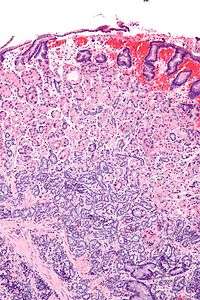

A gastrinoma is a tumor in the pancreas or duodenum that secretes excess of gastrin leading to ulceration in the duodenum, stomach and the small intestine. There is hypersecretion of the HCl acid into the duodenum, which causes the ulcers. Excessive HCl acid production also causes hyperperistalsis, and inhibits the activity of lipase, causing severe diarrhea.

It is usually found in the duodenum, although it may arise in the stomach or pancreas. Those occurring in the pancreas have a greater potential for malignancy. Most gastrinomas are found in the gastrinoma triangle; this is bound by the junction of cystic and common bile ducts, junction of the second and third parts of the duodenum, and the junction of the neck and body of the pancreas.